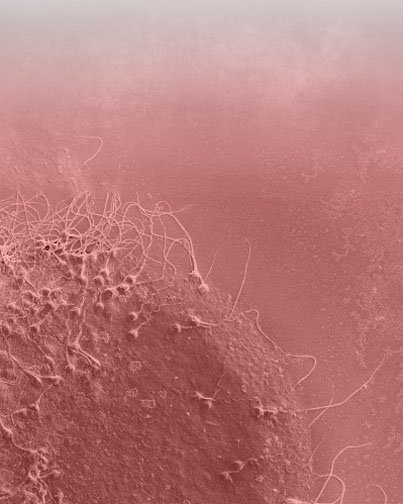

Stichting

Rafael Bernabeu

De maatschappelijke belangstelling van Instituto Bernabeu heeft een sociaal,

educatief, cultureel, wetenschappelijk en onderzoekbevorderende eigenschap.